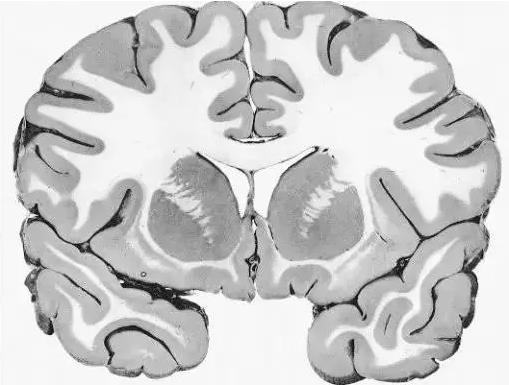

讓我們使用半球橫截面看看大腦的主要部分。因此,這是你腦袋里大腦的樣子:

現(xiàn)在,讓我們把大腦取出來,并刪除左半球,這讓我們能看清楚內(nèi)部。